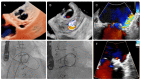

Background: Paravalvular leak occurs in 5-17% of patients following surgical valve replacement, more often in mitral position. The prognosis without treatment is poor. Percutaneous device closure represents an alternative to repeat surgery. The objective of this work is to evaluate the medium and long-term results in the percutaneous closure of PVL in mitral prosthesis.

Methods: This observational study is based on a retrospective registry including consecutive mitral PVL cases undergoing percutaneous closure at a single tertiary-care center from April 2010 to December 2020. The safety and efficacy results of the procedure, at 90 days and in the long term, were analyzed. Also, predictors of procedure failure and long-term events were identified.

Results: A total of 128 consecutive mitral paravalvular leak closure procedures were included. Technical success was achieved in 115 (89.8%) procedures. The presence of multiple PVLs was the sole factor that independently predicted procedural failure. Median follow-up of our sample was 41.8 months (mean 47.7 ± 35.7 months). Underlying hemolytic anemia as the indication for PVL closure, a recent admission for decompensated HF, and lack of improvement in functional class emerged as consistent predictors of MACE and death during long-term follow-up, while lack of procedural success during the first PVL procedure and chronic kidney disease were also associated with MACE during follow-up.

Conclusions: Percutaneous mitral PVL closure displayed high technical and procedural success rates, with an acceptable safety profile, in a high-risk population. Percutaneous mitral PVL closure achieved an improvement in short- and long-term functional class and a reduction of hemolysis in the vast majority of patients. In addition, long-term survival in our study was good, in particular for patients undergoing successful PVL closure procedures.